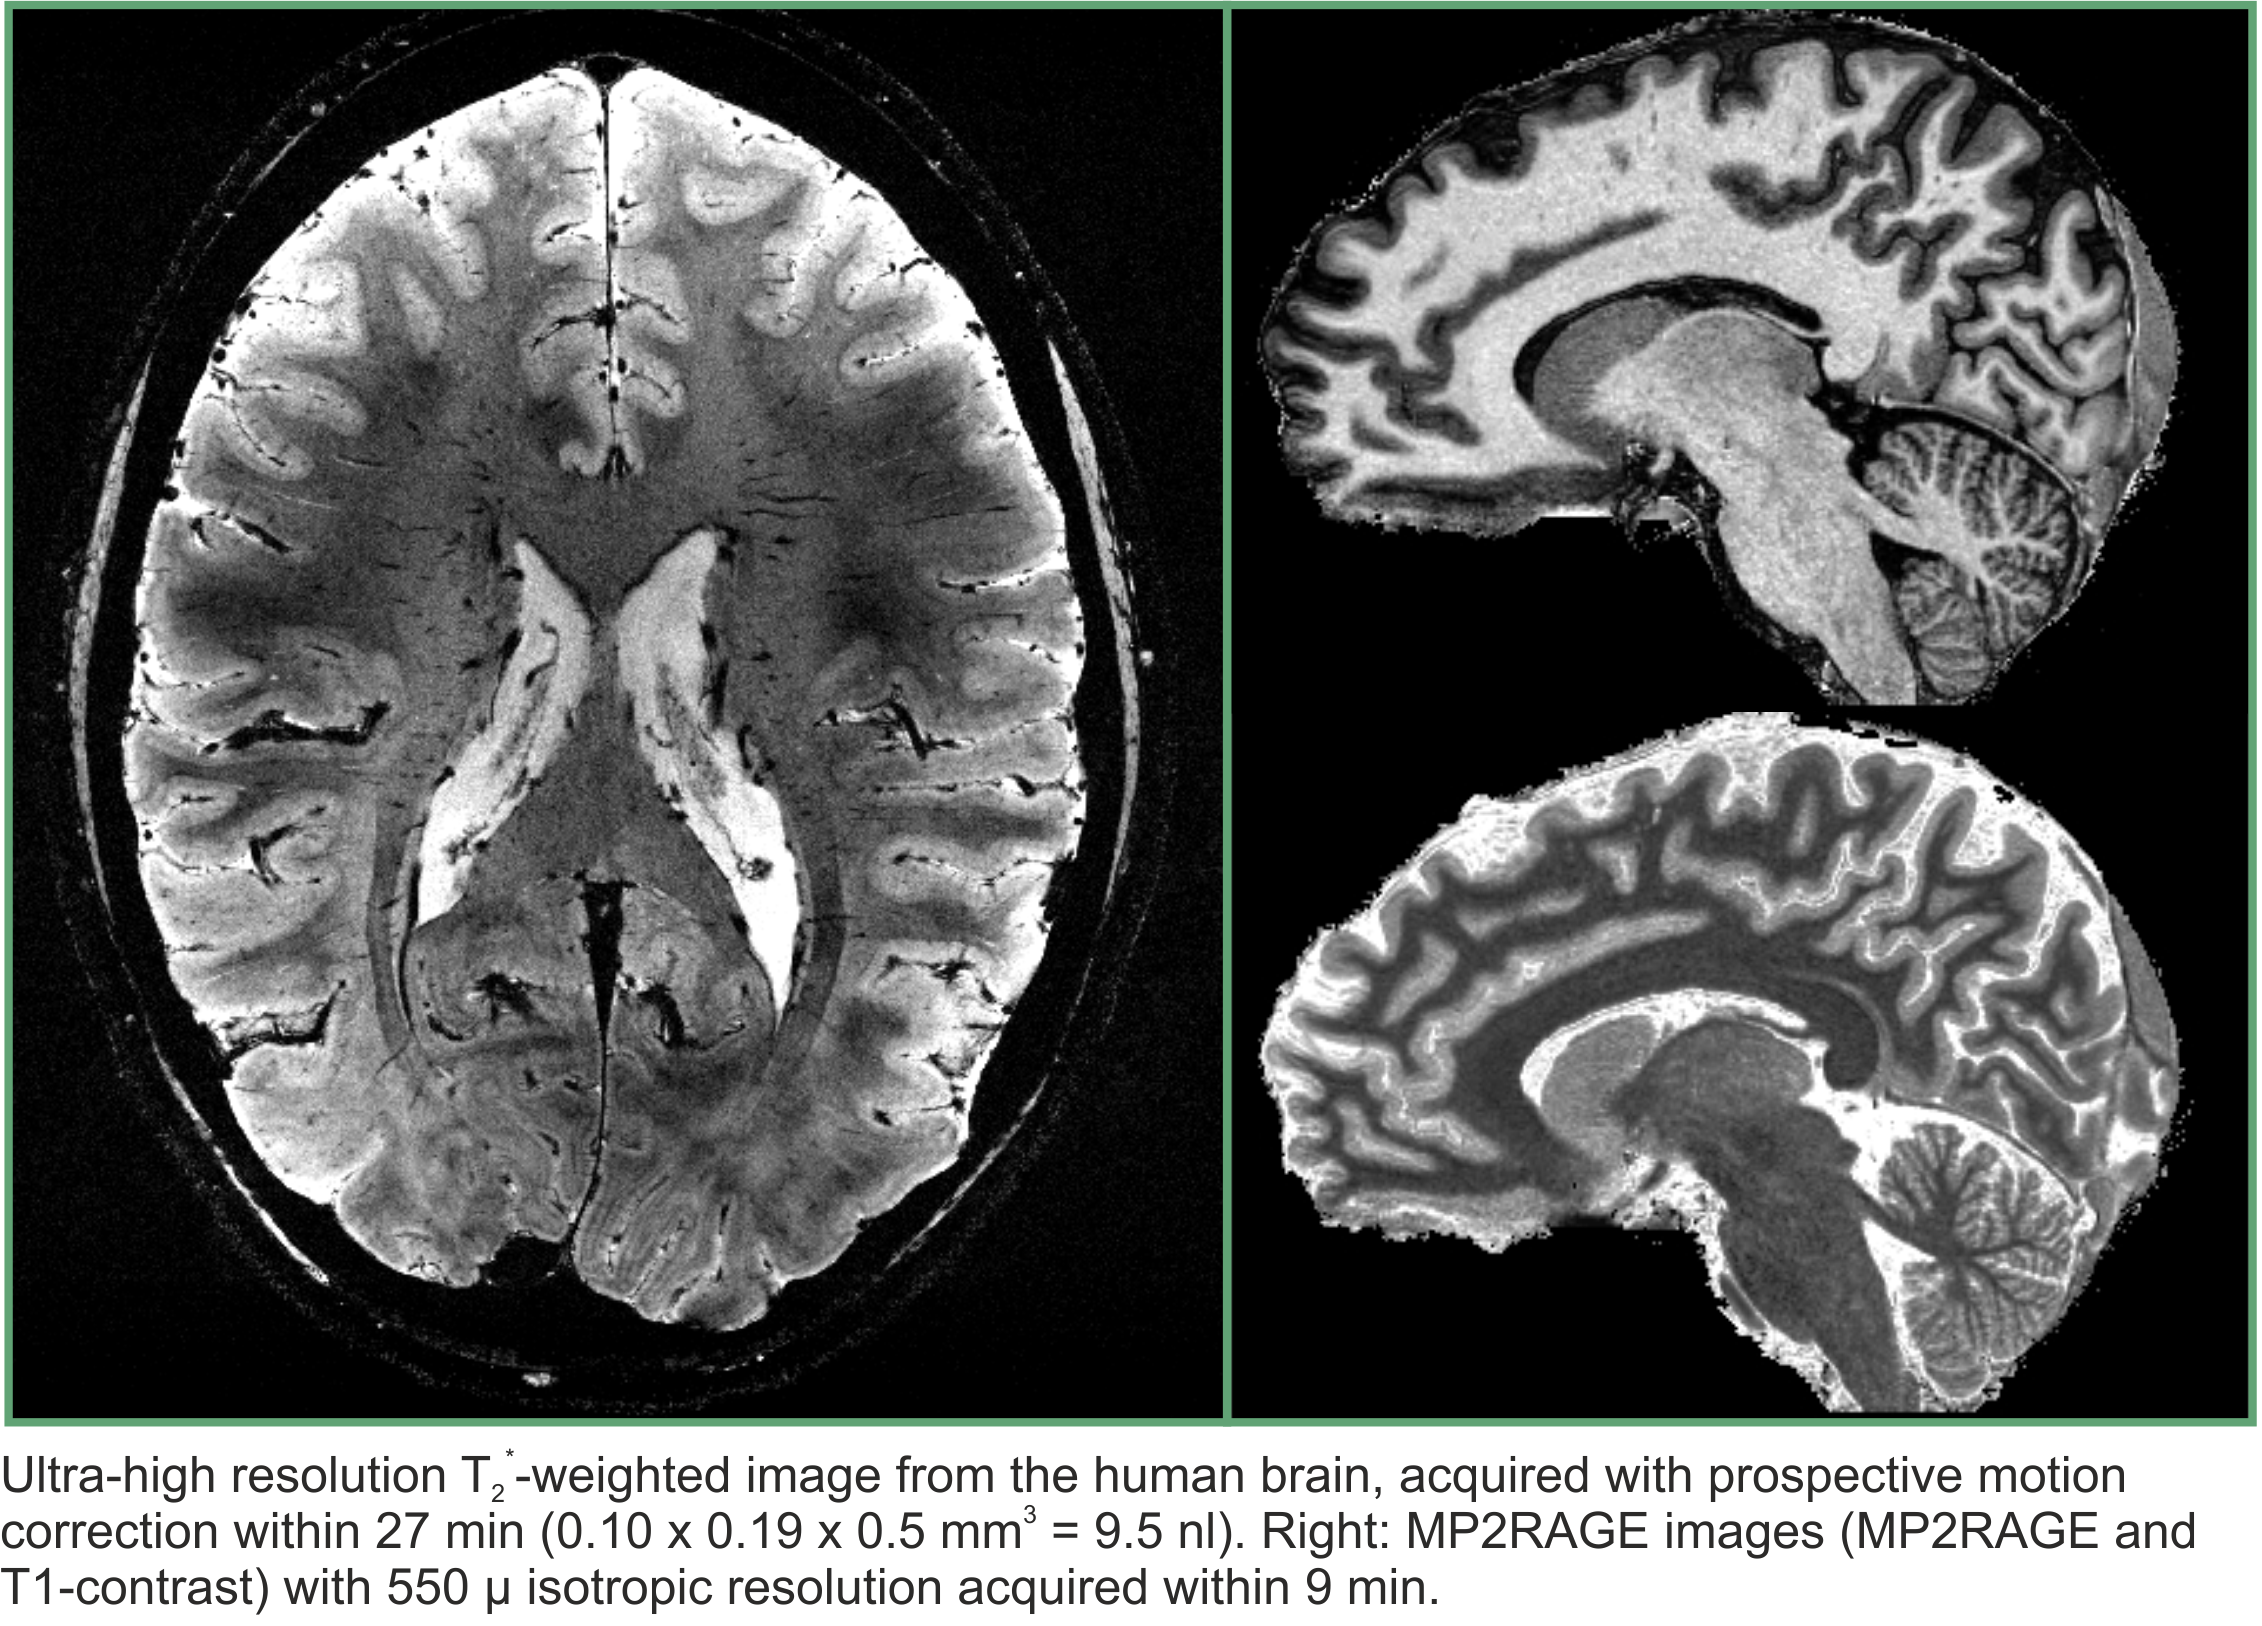

In this article, Shajan and colleagues explored the advantages inherent in transmit and receive arrays and combined them to image the human brain at 9.4T. Arranging transmit array elements in multiple rows provides an additional degree of freedom to correct for B1+ field inhomogeneities and to achieve whole-brain excitation at ultrahigh field strengths. Receive arrays shaped to the contours of the anatomy increase the signal-to-noise ratio of the image. Using a combination of the two in the brain achieved a two-fold increase in signal-to-noise ratio when compared with a 16-channel elliptic microstrip transceiver array.